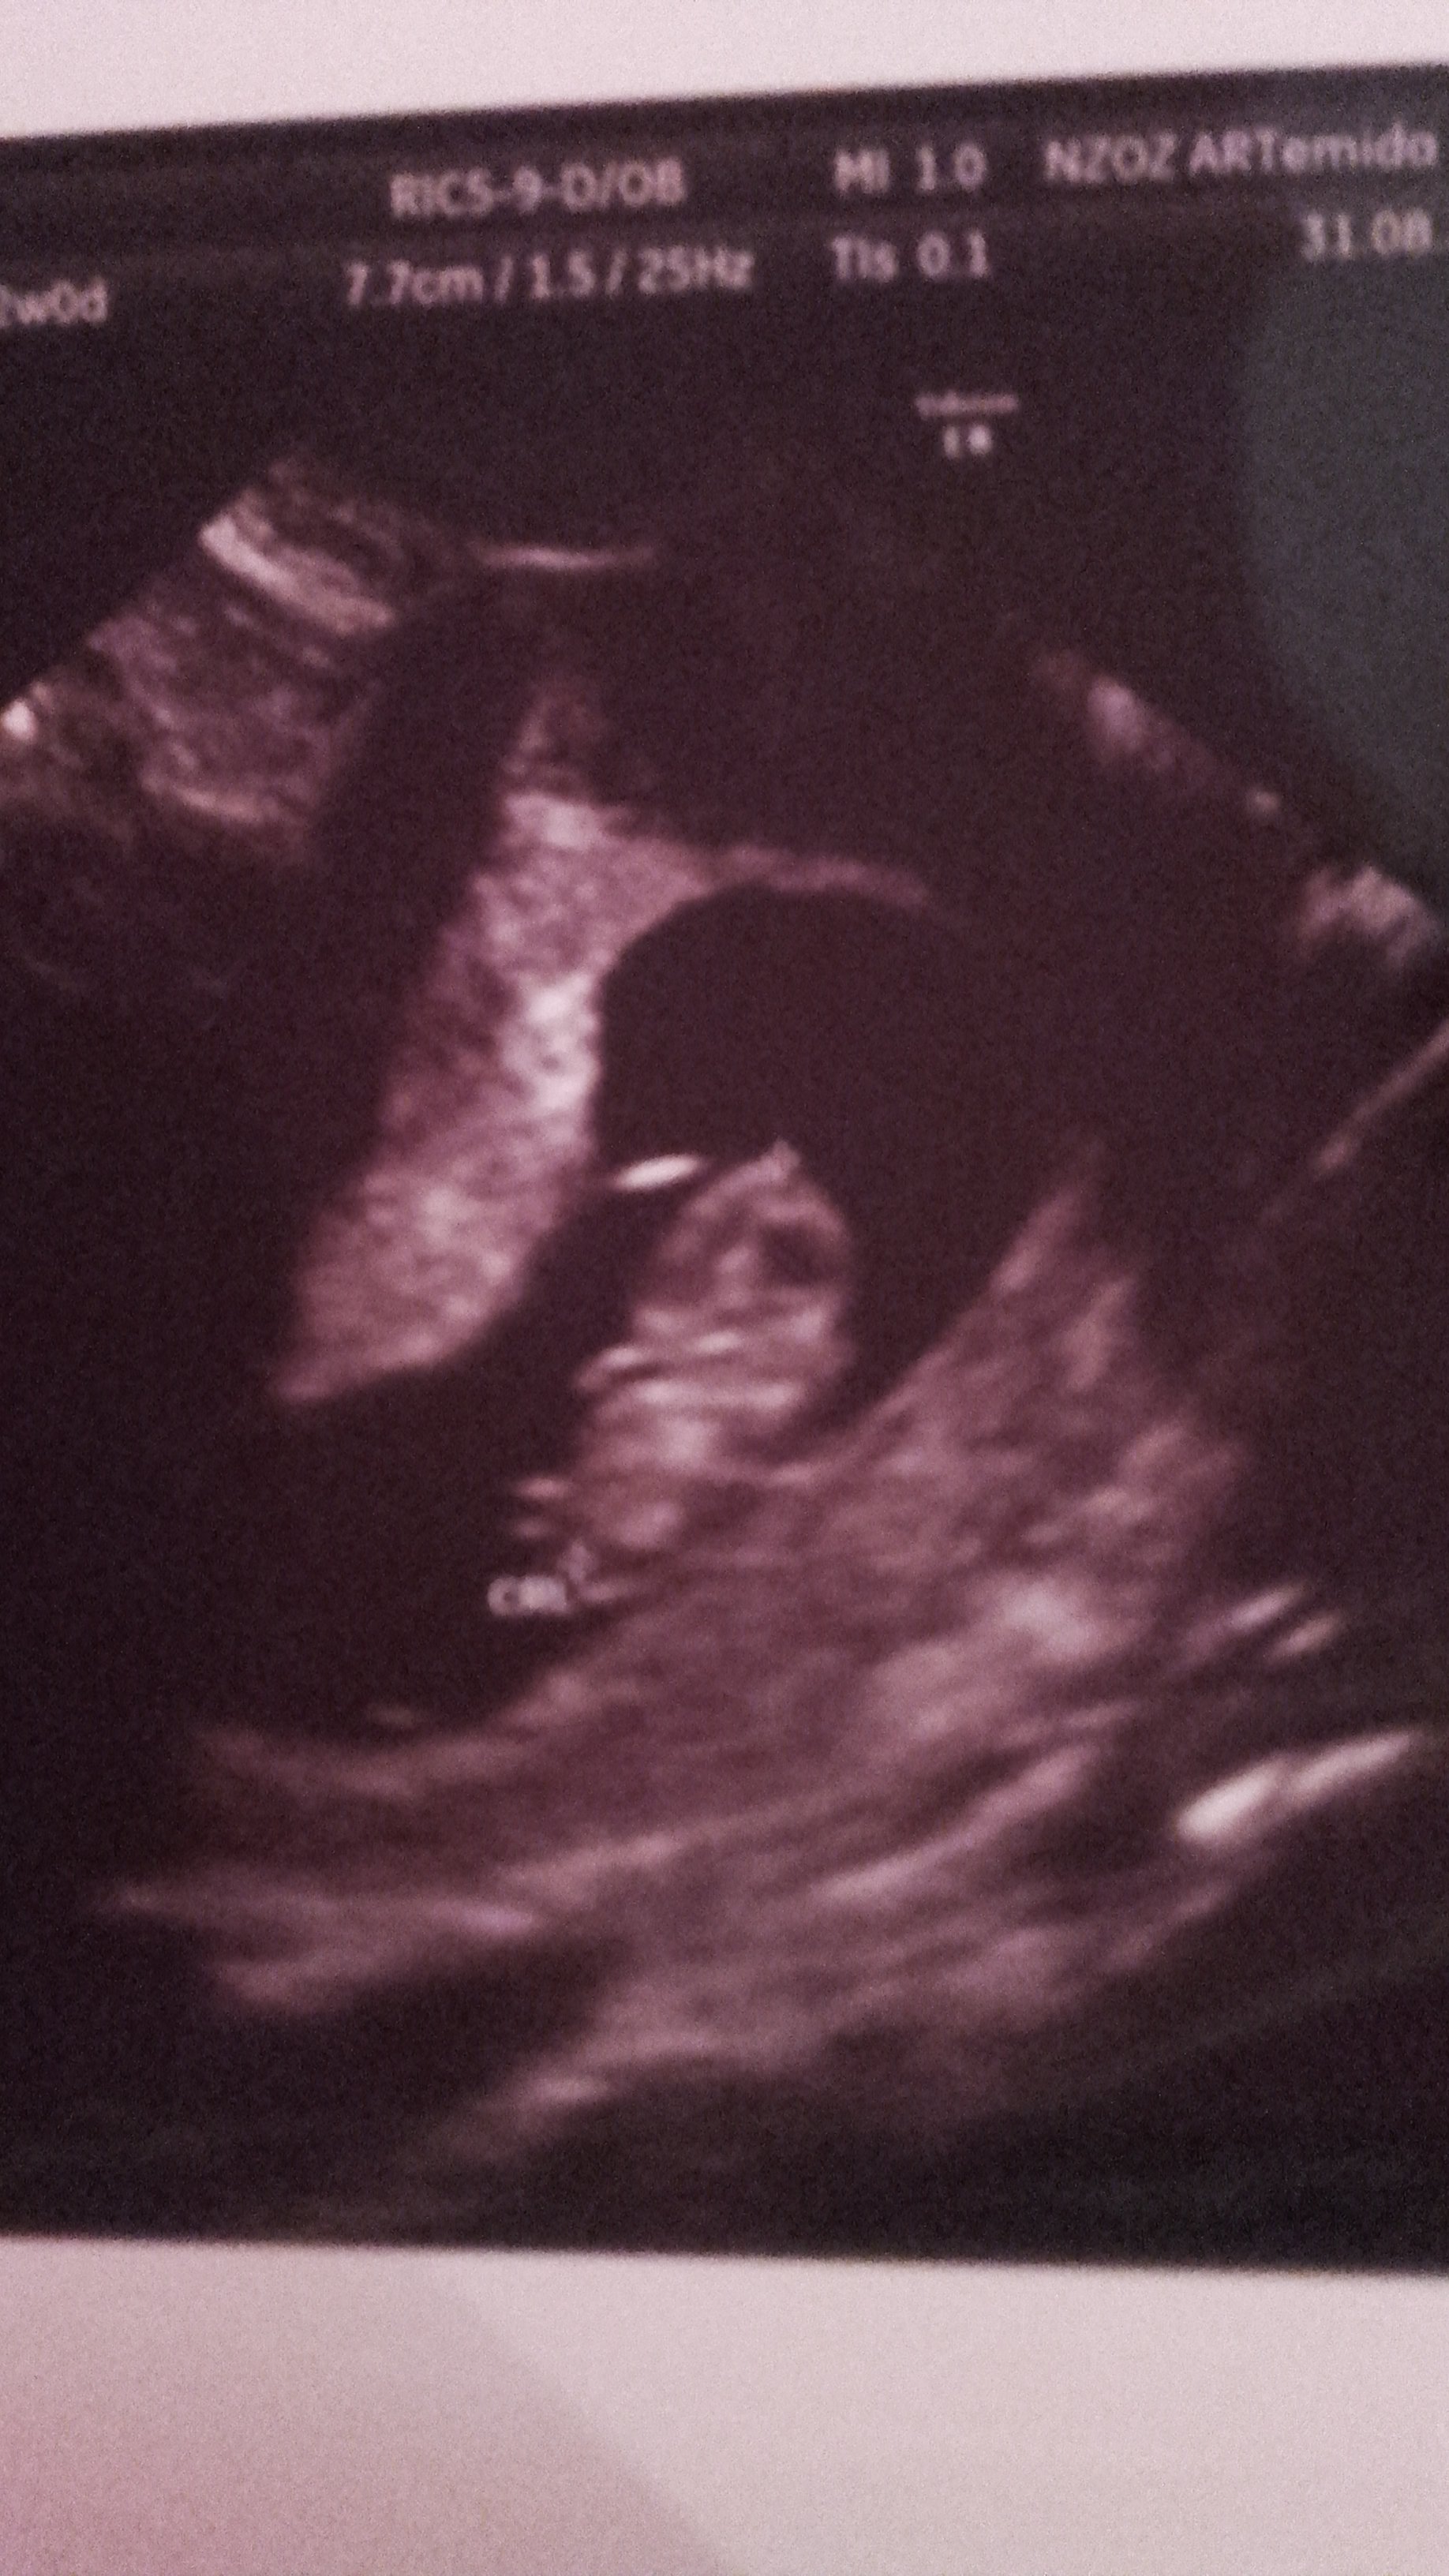

Jak dzis zobaczylam swoja dzidzie na usg to az mi cisnienie skoczylo ma 2 cm jest wszystko w porzadku. Dzis dostalam karte ciazy. Zobacz załącznik 770718 Zobacz załącznik 770719